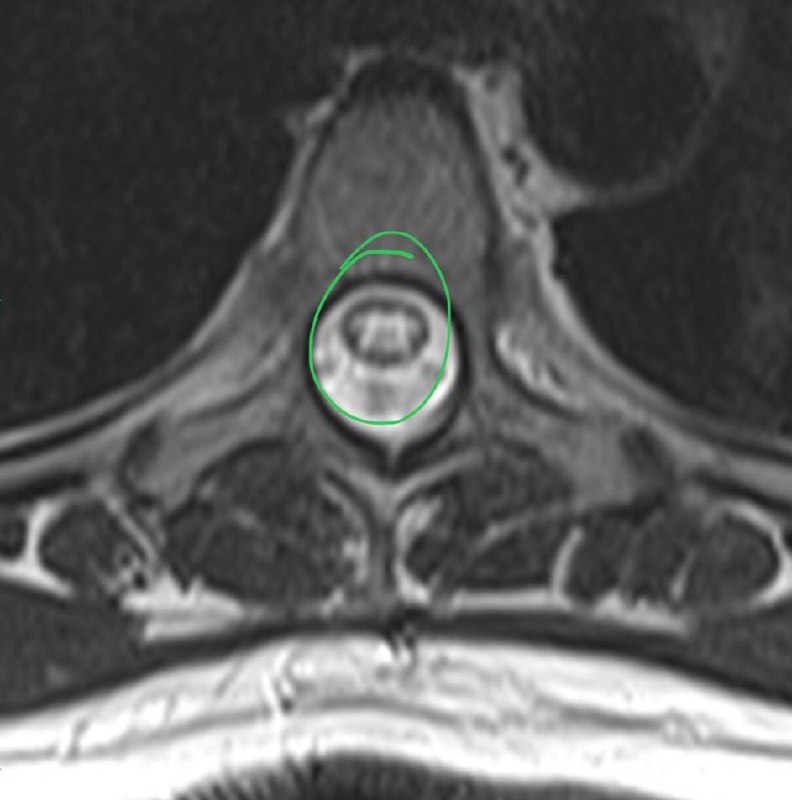

Выкладываю лекцию про центральный канал спинного мозга на сегодняшнем конгрессе по нейроонкологии.

Попросили вновь выложить лекцию про центральный канал спинного мозга, выполняю просьбу.